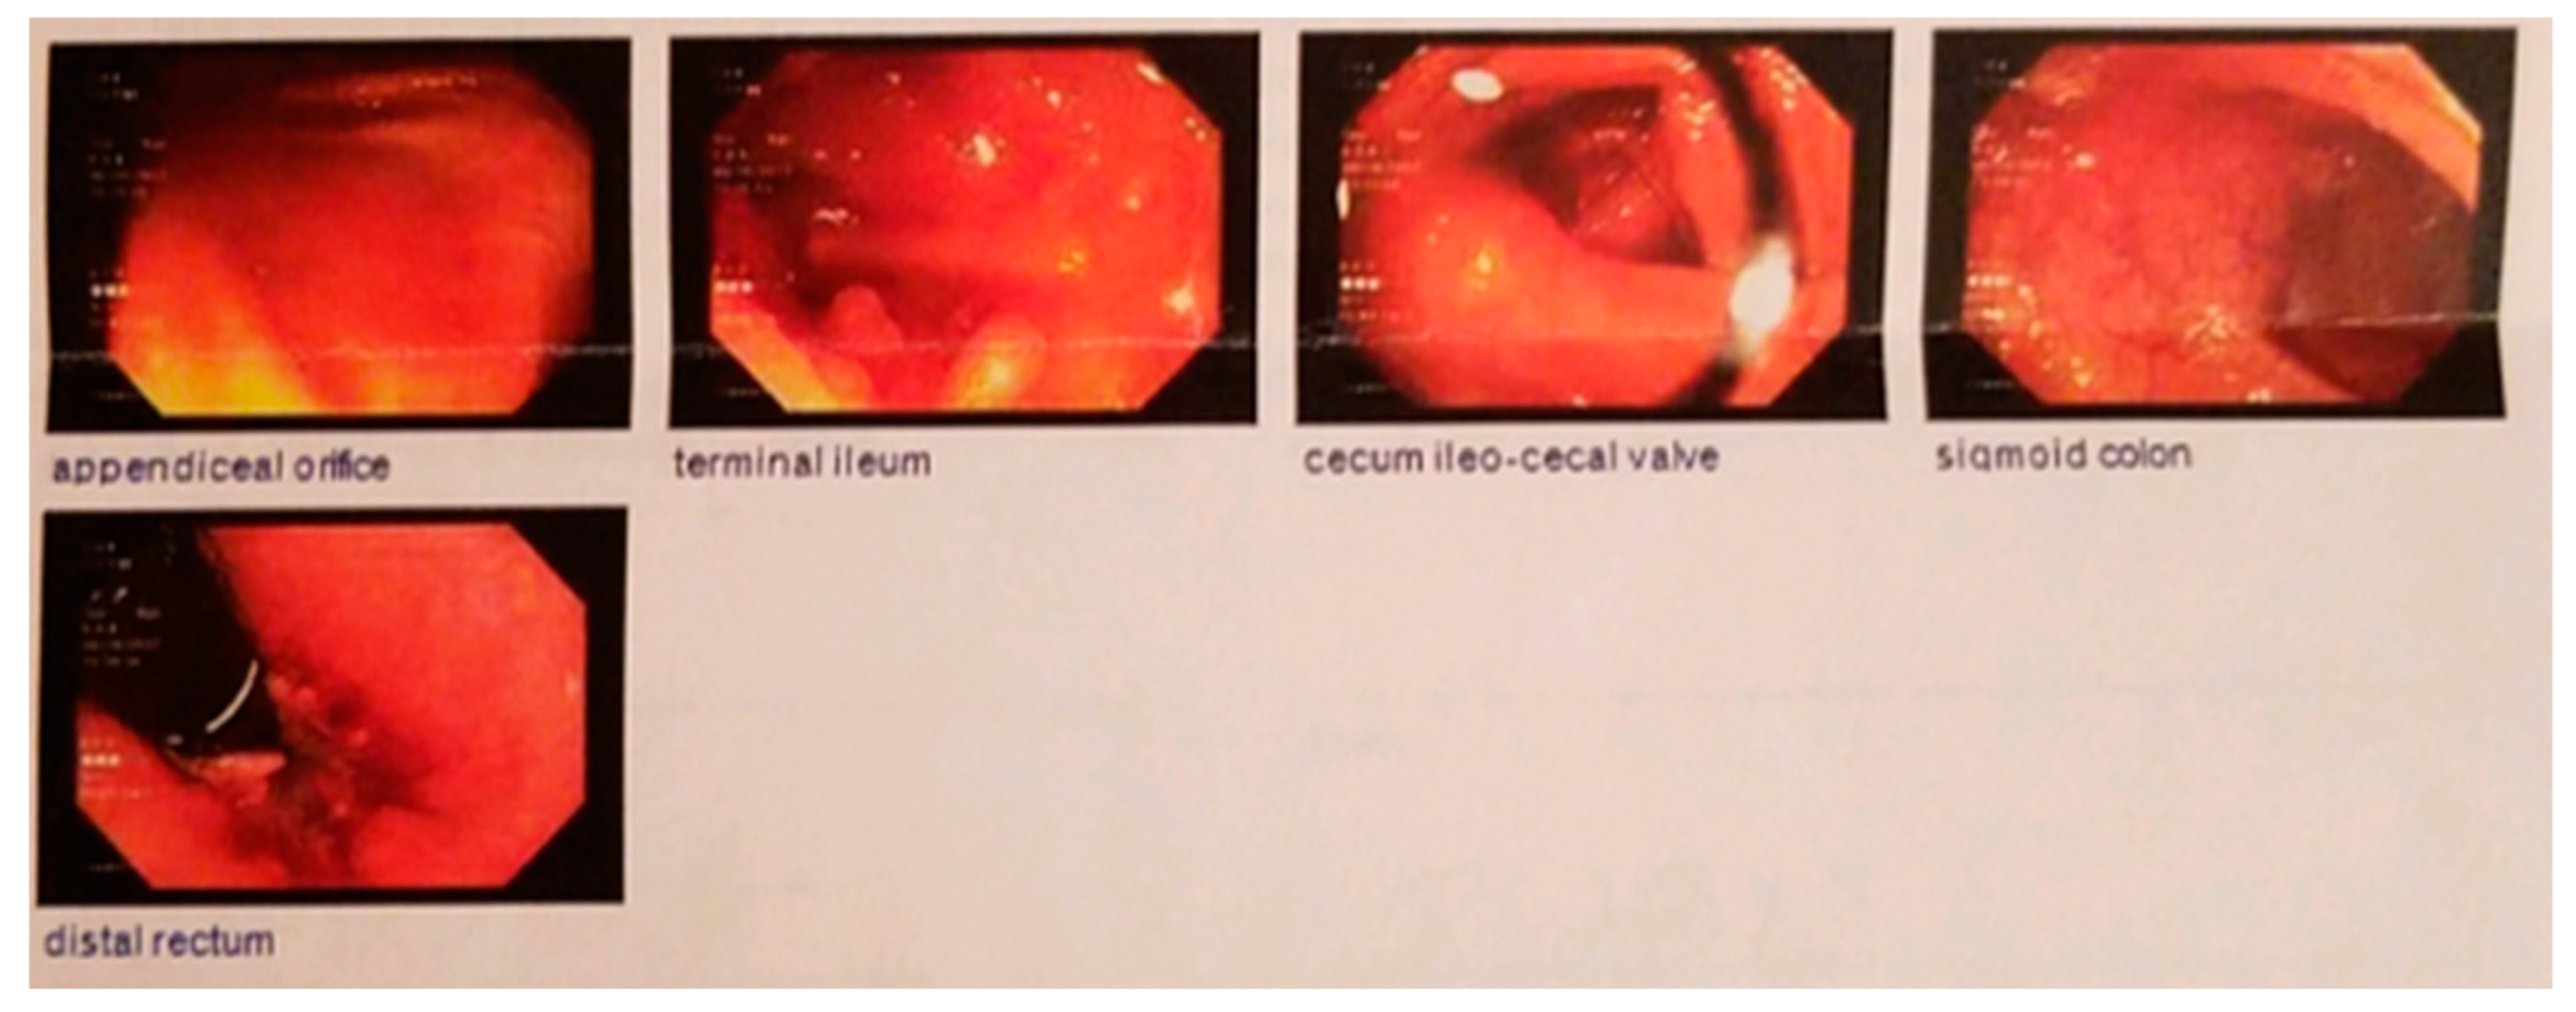

2. Case